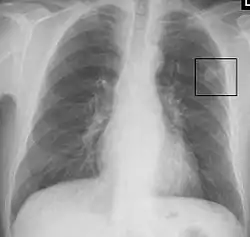

- Рак легень

- Рак верхівки легені з синдромом Панкоста

- Конвенційна рентгенодіагностика — на сьогодні найдоступніший метод, що дозволяє відносно успішно досліджувати органи грудної порожнини, черевної порожнини та кісткової системи організму.